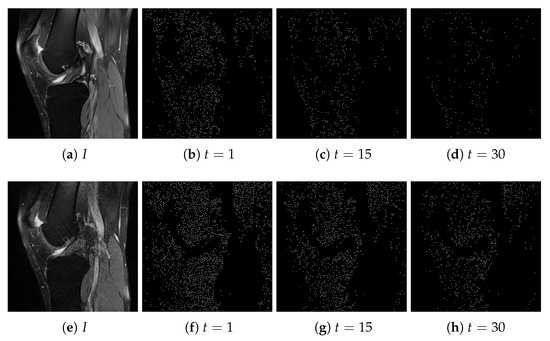

2. Proposed Image Quality Measure